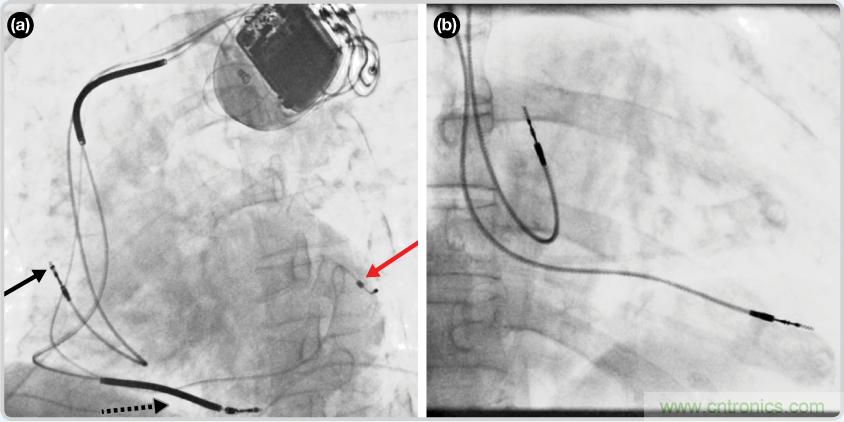

CRT器件在圖4(a)中的透視圖像中可以看見。醫師就是利用這種影像來放置導聯線的。對于非專業人士來說,這種影像是很難解讀的。可以看到心臟淡淡的輪廓——這是搏動中的心臟的靜態視圖。起搏器位于右心房上,心臟頂點指向右下方。在這個典型的導聯線放置實例中,黑色箭頭指向右心房導聯線。虛線黑色箭頭指向右心室導聯線。紅色箭頭標示的導聯線只能看到一部分,這是左心室導聯線(紅箭頭指向電極尖端)。圖4(b)展示的是雙腔起搏器的典型導聯線放置透視圖像。右心房導聯線指向上方,置于右心房中。右心室導聯線則位于右心室頂部。

檢測并區分心臟起搏偽像

圖4. 起搏器導聯線放置的透視圖像3 (a). 單腔起搏器;(b).雙腔起搏器